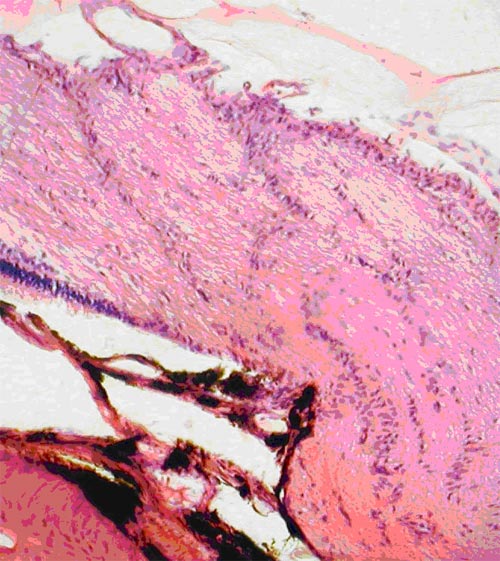

В группе кроликов № 2 с АИГ наблюдалось разрежение клеток в ганглиозном слое: они значительно дальше располагались друг от друга, на некотором протяжении слой выглядел, как безъядерный, цитоплазма клеток не визуализировалась (рис. 3).

Экспериментальная глаукома. Снижение количества нейронов в ганглиозном слое у кроликов за счет мелких и средних клеток. Окраска гематоксилином и эозином. Ув.  200

Рис. 3. Экспериментальная глаукома. Снижение количества нейронов в ганглиозном слое у кроликов за счет мелких и средних клеток. Окраска гематоксилином и эозином. Ув. 200

Общее количество ганглиозных клеток было статистически достоверно снижено (р<0,001) по сравнению с группой интактных кроликов и составило 279,00±5,18. Из них мелкие составили 93,50±2,74; средние - 123,83±1,82; крупные - 61,67±3,91. Обнаружено, что при развитии глаукомы снижение количества ганглиозных клеток сетчатки происходило за счет мелких и средних: процент соотношения мелкие/ средние/крупные составил 33/44/22. Резкая атрофия клеток в ганглиозном слое, от каждой из которых отходил аксон, заметно отразилась на толщине их слоя. Толщина слоя аксонов статистически достоверно (р<0,001) была снижена по сравнению с нормой и составляла 78,85±1,86 мкм (рис. 4).